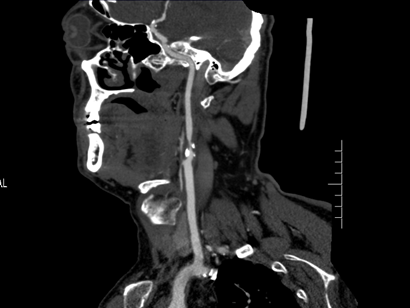

▲ 颈动脉硬化狭窄

这可急坏了张大爷,经邻居介绍求助于郑州大学五附院血管外科王兵教授,检查后脑梗死的“真凶”终于现了身——右侧颈动脉重度狭窄!